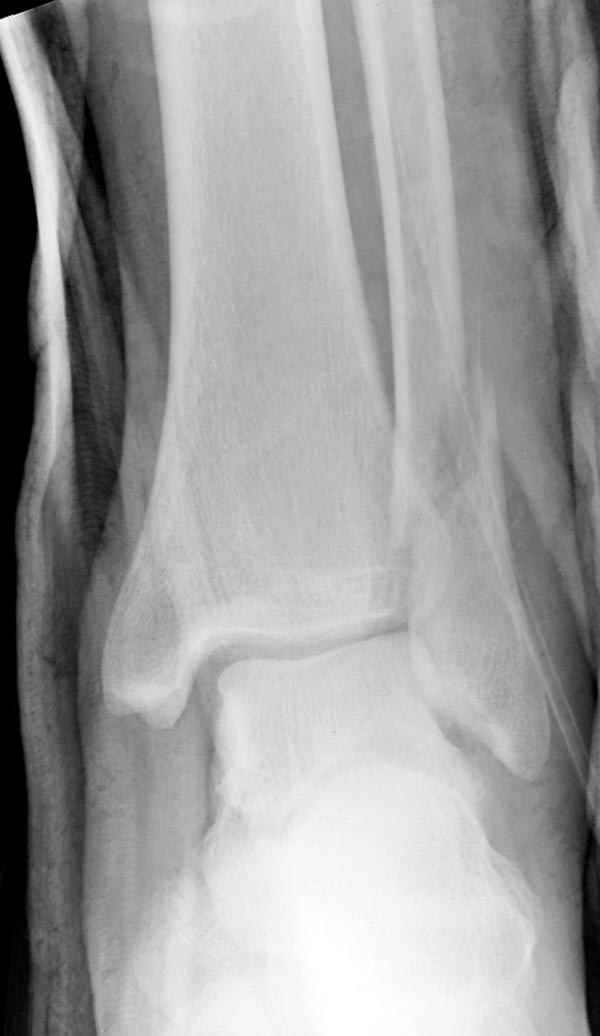

Тему неоднократно разбирали (см. архив), как всегда, недостаточны ренгенологические исследования - кроме прямого и боковых снимков, еще нужна косая ренгенограмма для определения ankle mortise, без мортиз снимка трудно определить высоту и ротацию малоберцовой. (снимки)

Ренгенология даст ответ как классифицировать перелом, на сегодня применяется классификация “Lauge Hansen fracture classification SER supination-external rotation или supination-eversion classification Danis

Weber А, В, С.”

Показания для фиксации: укорочения и ротация малоберцовой, особенно обращают внимание на любой подвывих таранной кости: неустраненый подвывих впоследствии приводит к раннему артрозу. Задний край фиксирует тогда, когда перелом составляет около 25% суставной поверхности голеностопного сочленения и смещение более 2мм.

По снимку ваш случай относится к Weber В, фиксацию производят восстановлением длины малоберцовой кости, под ренгеном (ЭП)контролем, для этого я предпочел бы латеральный доступ, остеотомия по линии перелома, удлинение малоберцовой засчет скоса линии остеотомии, компрессия “lag technique”по линии остеотомии и фиксацию провести латеральной пластиной. Отдельный задний доступ, остеотомия по линии перелома, репозиция и фиксация заднего края вашим предпочтительным методом: 3.5мм шурупом с шайбой или пластиной Antiglide Butress

method. При восстановленном суставе, уменьшится медиальная щель, а при Weber В повреждается только передне-нижняя межберцовая связка синдесмоза, повреждение которой приводит к наружной ротации

малоберцовой, но после восстановления всех смещений, связка автоматический приближается к исходному и нет необходимости восстановления синдесмоза.